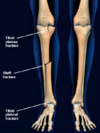

Tipos de fracturas de tibia

* Fractura de meseta tibial * Fractura del eje tibia-peroné * Fractura de pilón tibial (tobillo)

¿Qué tipos de fractura puede haber en el eje tibia-peroné? | Pueden ocasionar:

Transversa, oblicua, espiral, mariposa | Sx compartimental